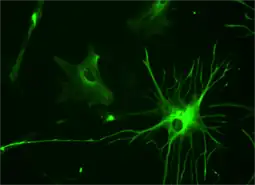

Microglia

Microglia are specialized macrophages capable of phagocytosis that protect neurons of the central nervous system.[22] They are derived from the earliest wave of mononuclear cells that originate in yolk sac blood islands early in development, and colonize the brain shortly after the neural precursors begin to differentiate.[23]

These cells are found in all regions of the brain and spinal cord. Microglial cells are small relative to macroglial cells, with changing shapes and oblong nuclei. They are mobile within the brain and multiply when the brain is damaged. In the healthy central nervous system, microglia processes constantly sample all aspects of their environment (neurons, macroglia and blood vessels). In a healthy brain, microglia direct the immune response to brain damage and play an important role in the inflammation that accompanies the damage. Many diseases and disorders are associated with deficient microglia, such as Alzheimer's disease, Parkinson's disease and ALS.